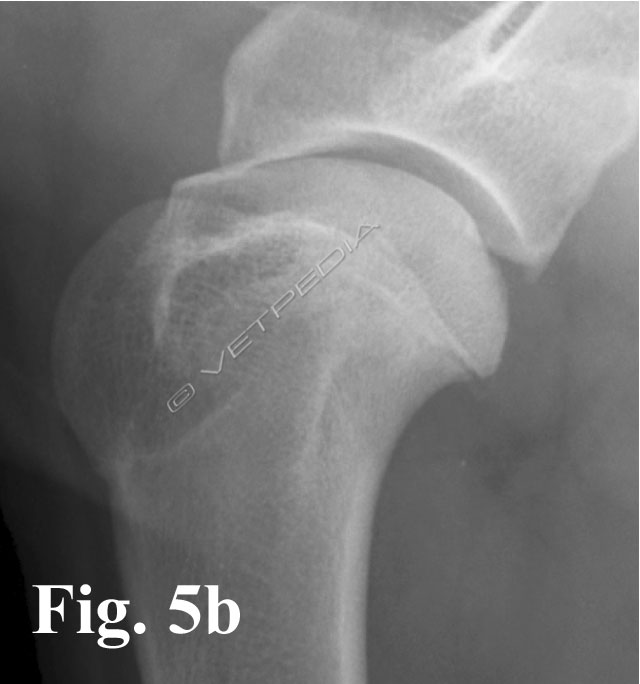

La corretta diagnosi di queste forme iniziali ci consente di indirizzare il paziente verso un approccio chirurgico o conservativo. In caso di diagnosi di OC, è consigliabile monitorare radiograficamente la lesione, con controlli a distanza di circa 2/3 settimane, in modo da valutarne l’evoluzione: guarigione spontanea versus formazione e sollevamento del lembo osteocondrale. Nei casi in cui la lesione è localizzata medialmente, la proiezione medio-laterale neutra potrebbe non consentirci di evidenziare il difetto osteocondrale o di sottostimarne l’estensione (Fig. 5a). E’ consigliabile a tal proposito eseguire una proiezione medio-laterale con rotazione esterna dell’arto, in modo da esporre al fascio radiogeno tangente anche le lesioni localizzate nel comparto mediale (Fig. 5b). Un’altra evenienza è rappresentata dalla migrazione del lembo osteocondrale che, come precedentemente accennato, nei casi più fortunati potrebbe andare incontro a riassorbimento spontaneo oppure comportarsi da “topo” o “tofo” articolare (Fig. 6). La sede dove più frequentemente tende a localizzarsi è rappresentata dal recesso caudale dell’articolazione (vedi Fig. 2), in casi meno fortunati potrebbe migrare nel comparto craniale, più precisamente nella doccia bicipitale, e determinare un’irritazione meccanica al tendine del muscolo bicipite brachiale. In quest’ultimo caso i sintomi dipenderanno dallo sviluppo di una tenosinovite bicipitale.